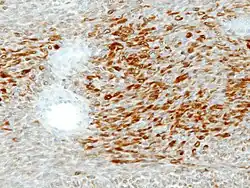

Microscopie

L'adénome pléomorphe est constituée par deux populations cellulaires intriquées d'où son autre nom de « tumeur mixte » :

- Composante épithéliale et myoépithéliale[1].

- Composante conjonctive de type myxoïde[1].

Double contingent épithélial et conjonctif. HE, x400.

Immunohistochimie

_S-100.jpg)